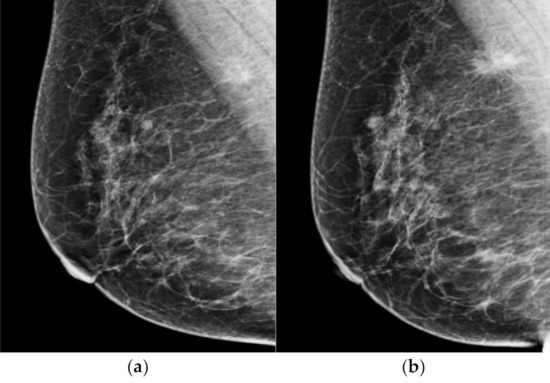

Figure 2.

Representative case of missed cancer detected by AI-CAD. A 67-year-old woman had a focal asymmetry with increased number of calcifications in diagnostic mammogram (a). After biopsy, this lesion was confirmed as invasive carcinoma. When the two radiologists reviewed the prior mammogram performed 12 months ago (b), asymmetry visible on CC view and several calcifications were retrospectively detected at the same location. When the AI-CAD was retrospectively applied, the AI-CAD identified the exact location of lesion in the diagnostic mammogram (c) and prior mammogram (d).